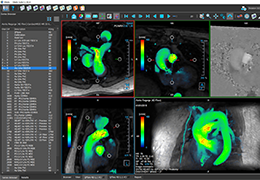

View X-Ray CT & MRI Scans Fast and Easily

Designed for surgeons, Pro Surgical 3D makes it easy to view patient scans quickly. Pro Surgical 3D facilitates the optimal 3D treatment and assessment workflows based on X-ray CT and MRI scans – and best of all, it’s FREE!

Traditional multi-planar slicing

High-quality and fast 3D reconstruction and 3D rendering

Performs 3D reconstruction and volume rendering.

Multi-planar slicing.